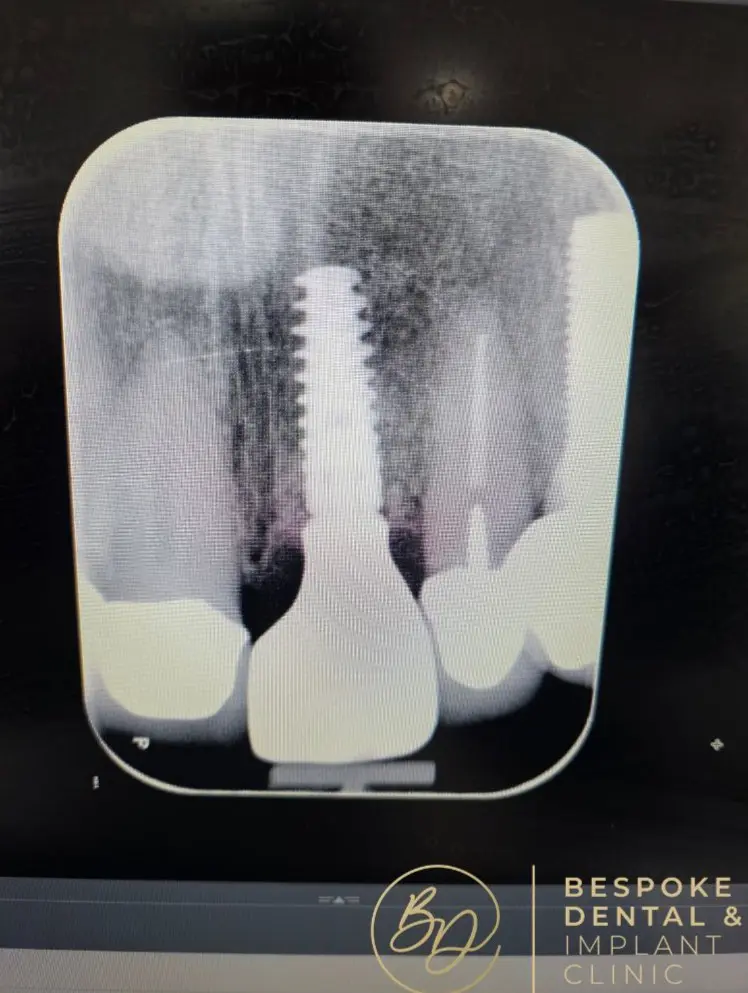

A dental implant is a screw-like metal post inserted into the jawbone. It acts as a natural tooth root and serves as a foundation for the replacement tooth, a custom-made dental crown that sits atop the implant.

The crown closely matches the size, shape, and colour of your natural teeth, ensuring it blends seamlessly with the surrounding teeth to give you a healthy, beautiful smile.